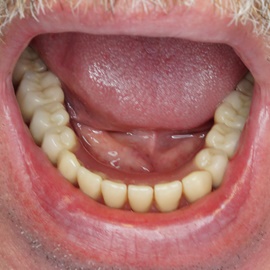

Brakujących pięć zębów dolnych w odcinku wargowym. Rekonstrukcja tkanek i rehabilitacja protetyczna.